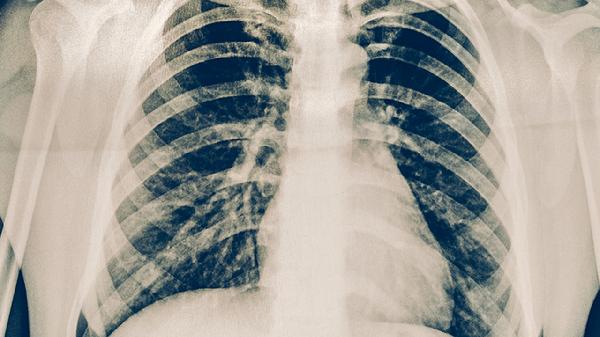

活動(dòng)性肺結(jié)核患者需進(jìn)行呼吸道隔離,佩戴口罩并單獨(dú)使用餐具。痰菌陽性者應(yīng)住院治療,居住環(huán)境保持通風(fēng),每日紫外線消毒。密切接觸者需接受結(jié)核菌素試驗(yàn)和胸部X線篩查。

結(jié)核病密切接觸者應(yīng)每半年進(jìn)行胸部X線檢查。長期使用免疫抑制劑者、塵肺患者等高風(fēng)險(xiǎn)人群需每年篩查。出現(xiàn)咳嗽咳痰超過2周、低熱盜汗等癥狀時(shí),應(yīng)及時(shí)進(jìn)行痰涂片和結(jié)核菌素試驗(yàn)。